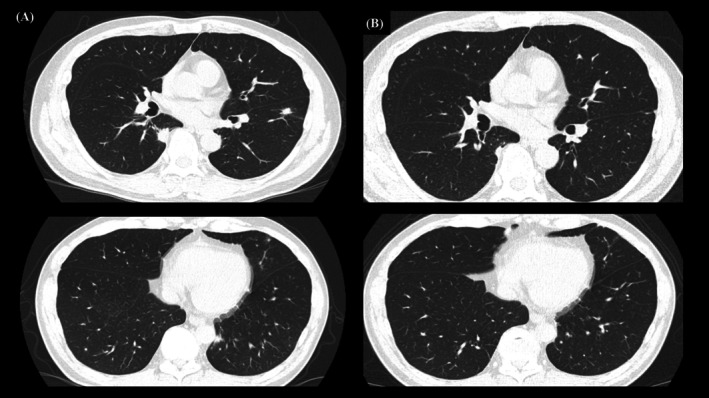

在全球范围内,梅毒病例一直在增加,并报告了肺部病变。然而,无症状的神经梅毒尚未被记录。这种情况往往不为人所知,其症状与其他传染性和非传染性肺部疾病相似。在被定义为梅毒的第二种形式的梅毒肺炎中,肌肉注射青霉素(2400万单位)仍然是治疗的金标准,预后良好。本文首次报道一例无症状性神经梅毒伴多发肺结节和臀部脂肪营养不良。如果快速血浆反应素(RPR)抗体滴度高且随访时RPR检测困难,可考虑脑脊液(CSF)检查以进一步评估无症状神经梅毒。本例RPR高表达(154 ruu),且由于患者工作性质(长途运输),短期随访困难。因此,采用脑脊液进行早期诊断和治疗。

Globally, syphilis cases have been increasing and pulmonary lesions have been reported. However, asymptomatic neurosyphilis has not been documented. This condition is often unrecognised and presents with symptoms similar to those of other infectious and non-infectious lung diseases. In syphilitic pneumonia, defined as a secondary form of syphilis, intramuscular injection of benzylpenicillin (24 million units) remains the gold standard for treatment, with a favourable prognosis. This report presents for the first time a case of asymptomatic neurosyphilis with multiple pulmonary nodules and buttock lipodystrophy. If rapid plasma reagin (RPR) antibody titres are high and RPR testing is difficult during follow-up, cerebrospinal fluid (CSF) examination may be considered for further evaluation of asymptomatic neurosyphilis. This case showed a high expression of RPR (154 R.U.) and given the nature of the patient's work (long-distance transportation), short-term follow-up was difficult. Therefore, CSF was performed to enable early diagnosis and treatment.